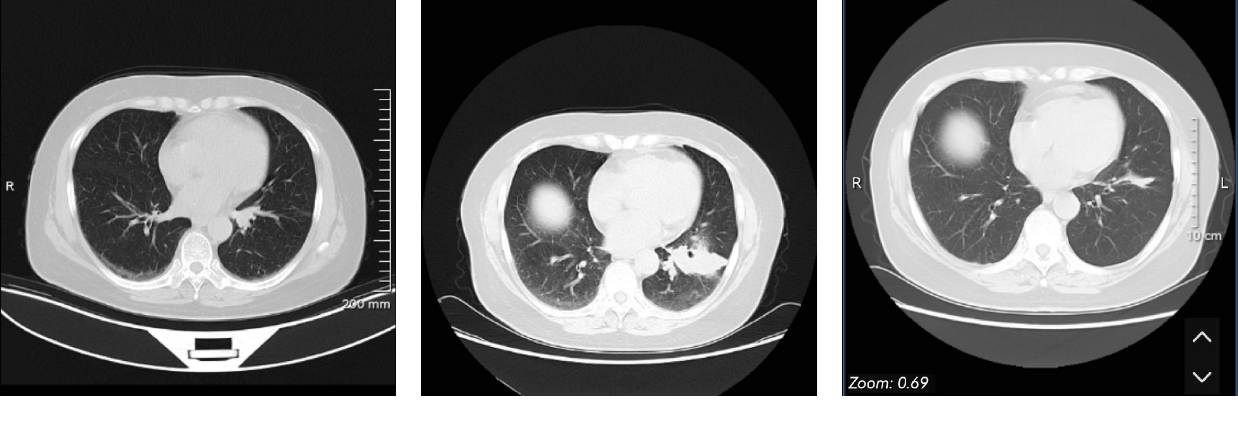

三化后10天,ct看不到原发灶。第40多天于中科院手术,术前检查没有问题。手术顺利。分期:t0n1,肺门淋巴一颗见癌(转移淋巴结免疫组化:pd1阴性),2b期

一个月ct,有新月型液性密度影与局部包裹液影,大夫认为无需处理。

计划年后去中科院复查,折腾那么远的原因是,术前ct还有些需要随访的问题,同一家医院好测量。这些问题术前大夫说,随访就好,不能确定性质意义,太小,也不好取病理,良性的可能大。这次复查可能要超出3个月一两周,碰上过年也没办法

10月28日骨扫结果